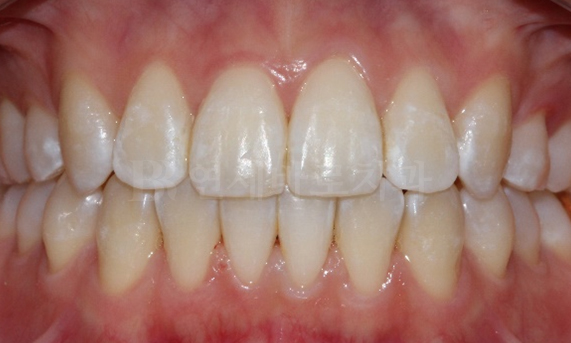

돌출입 교정 CASE

-